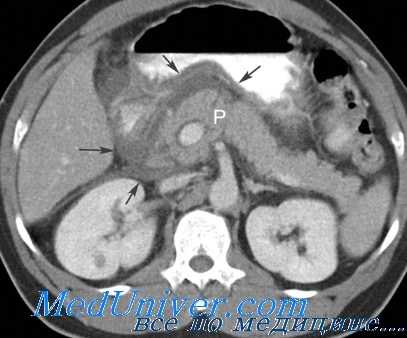

В диагностике тромботических осложнений определенную помощь могут оказать допплеросонография и ЯМР, подтверждающие снижение кровотока в питающих трансплантат сосудах, а в ряде случаев — ангиография.

Для определения острого отторжения полезными могут оказаться и некоторые инструментальные методы диагностики: радионуклидная сцинтиграфия, ангиография, ультразвуковая допплероскопия, ядерно-магнитный резонанс и компьютерная томография. Для верификации и определения типа отторжения требуется микроскопическое исследование трансплантата. Биопсия может быть проведена чрезкожно, под контролем УЗИ, компьютерной томографии или ЯМР.